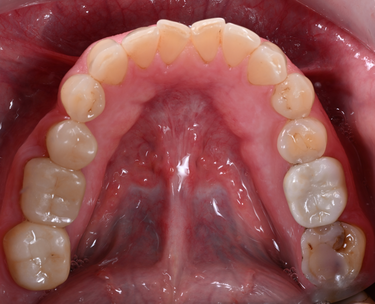

For this case, the patient was confident about her choice of having a BL4 bleach shade - bright but natural-looking teeth, therefore focus shifted to reproducting the milti-layered effects of a natural tooth after considering the BL selection of ingots (Figs. 1-2).

Figure 1: Inital Situation

• Placement of single crowns in the upper arch, and one three-units bridge in the posterior region.

• In the lower jaw, single crowns for the posterior teeth and veneers for the anterior teeth.